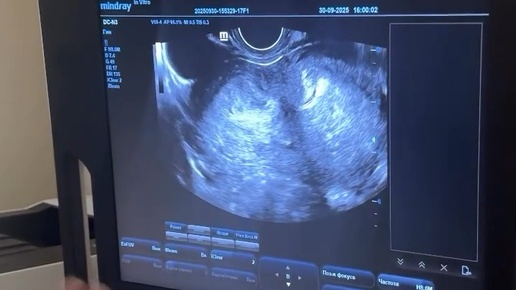

Две матки и два влагалища ,и такое бывает!